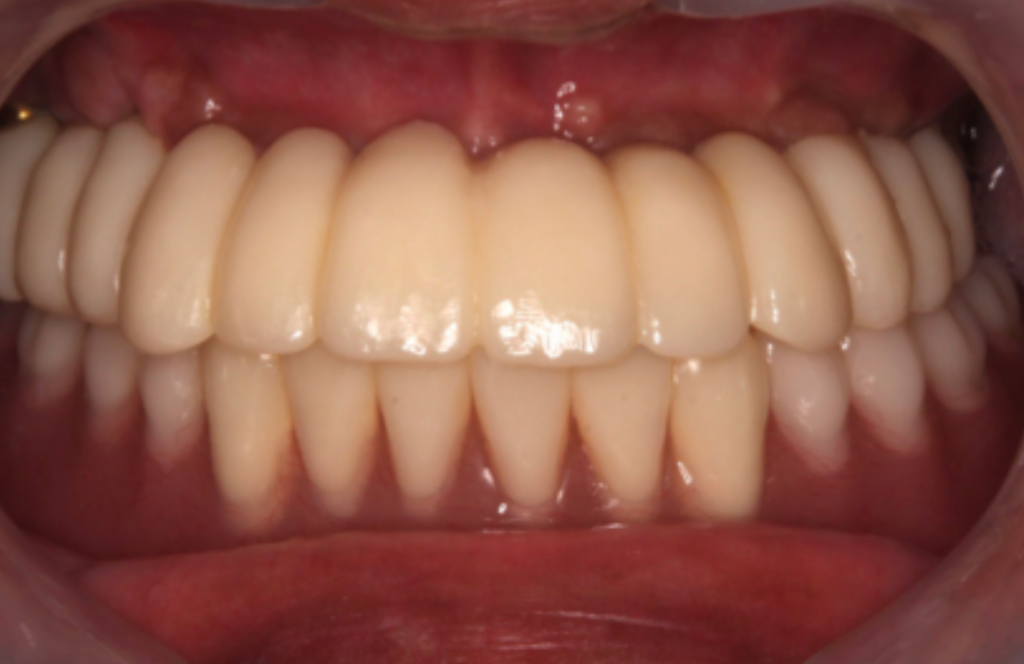

上部構造(被せ物)の製作・装着

院内ラボ(CAD/CAM)にて、歯の色や形を周囲の歯に合わせた精緻な被せ物を製作します。噛み合わせを確認しながら装着します。

インプラント治療は、天然歯に近い噛み心地を補うための選択肢の一つです。治療後の適切なセルフケアと定期的なメンテナンスを継続することで、長期にわたって安定した状態を保つことが期待できます。